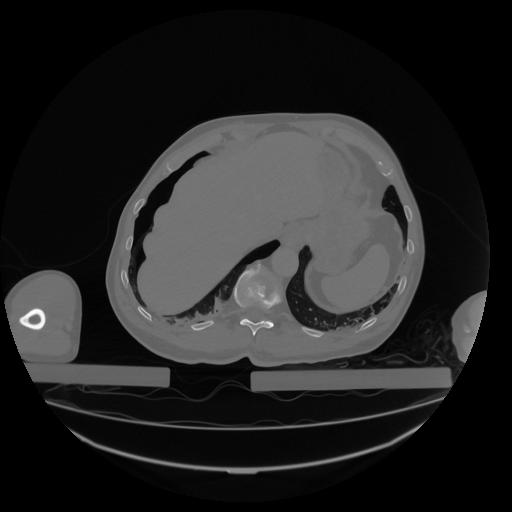

34 CUERPO,CE,Vol,1.0,CUERPO,,